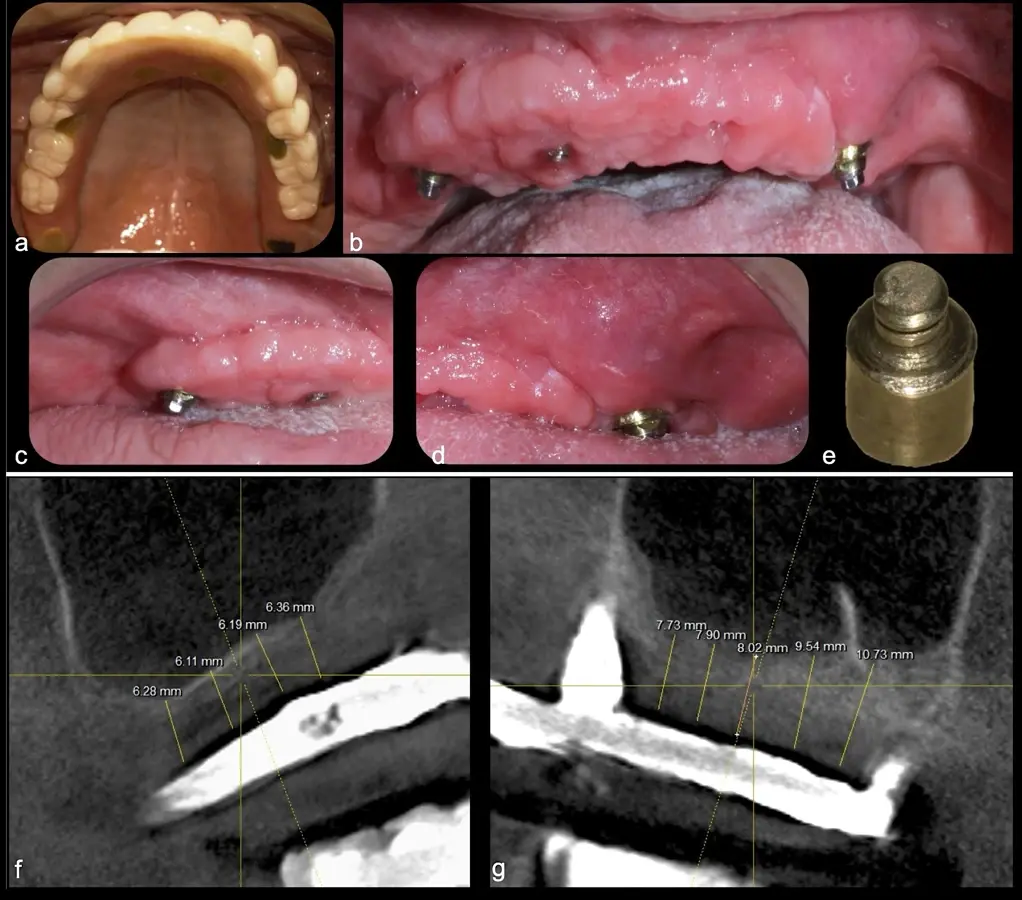

El levantamiento de piso de seno maxilar es una técnica quirúrgica aceptada previa o simultáneamente a la colocación de implantes dentales. La mayor evidencia científica refiere que si se tiene entre 0 -7 mm de altura ósea se debe realizar la elevación sinusal junto con injertos óseos; y a partir de los 8 mm, se hace más predecible la colocación simultánea de implantes dentales.1-3

El tipo de inserto a ser utilizado dependerá del espesor de la pared ósea. Si la pared es menor a 0.5 mm, es mejor utilizar insertos de desgaste para prevenir la ruptura de la membrana de Schneider; si el espesor es mayor a 0.5 mm, se puede utilizar insertos de corte de espesor medio (Figura 3).

El clínico puede retirar la tabla ósea o introducirla como “tienda de campaña” dentro del seno maxilar. En cualquiera de las alternativas, es importante evaluar la presencia de tabiques óseos y de la arteria postero alveolar superior.